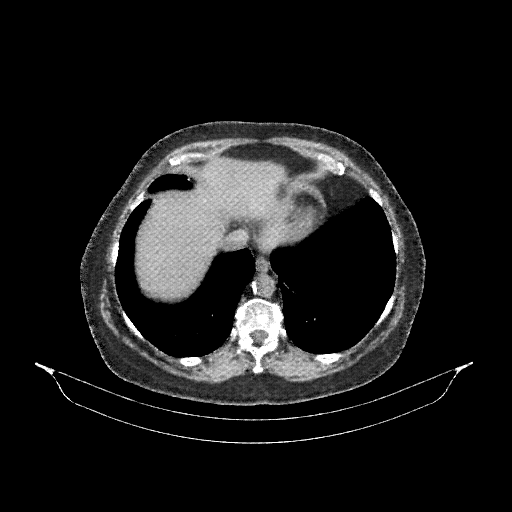

Generated VENOUS CT scan (A→B translation)

Full window (WL 1023.5, WW 4095 β†’ Low βˆ’1024, High +3071)

Mediastinum window (WL 40, WW 400 β†’ Low βˆ’160, High +240)